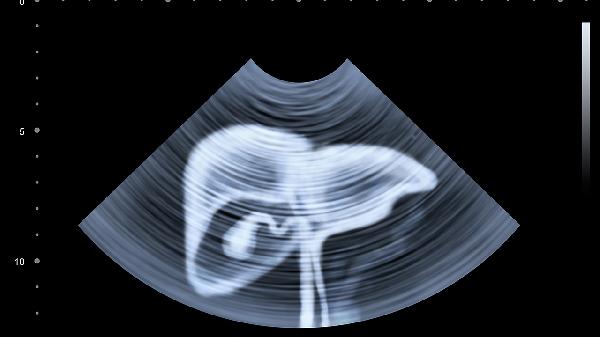

2、影像学特征

增强CT或MRI检查中,血管瘤呈典型"早出晚归"强化模式,边界清晰无浸润。肝癌表现为动脉期快速强化、静脉期快速消退,常伴有包膜侵犯和卫星病灶,部分病例可见门静脉癌栓形成。